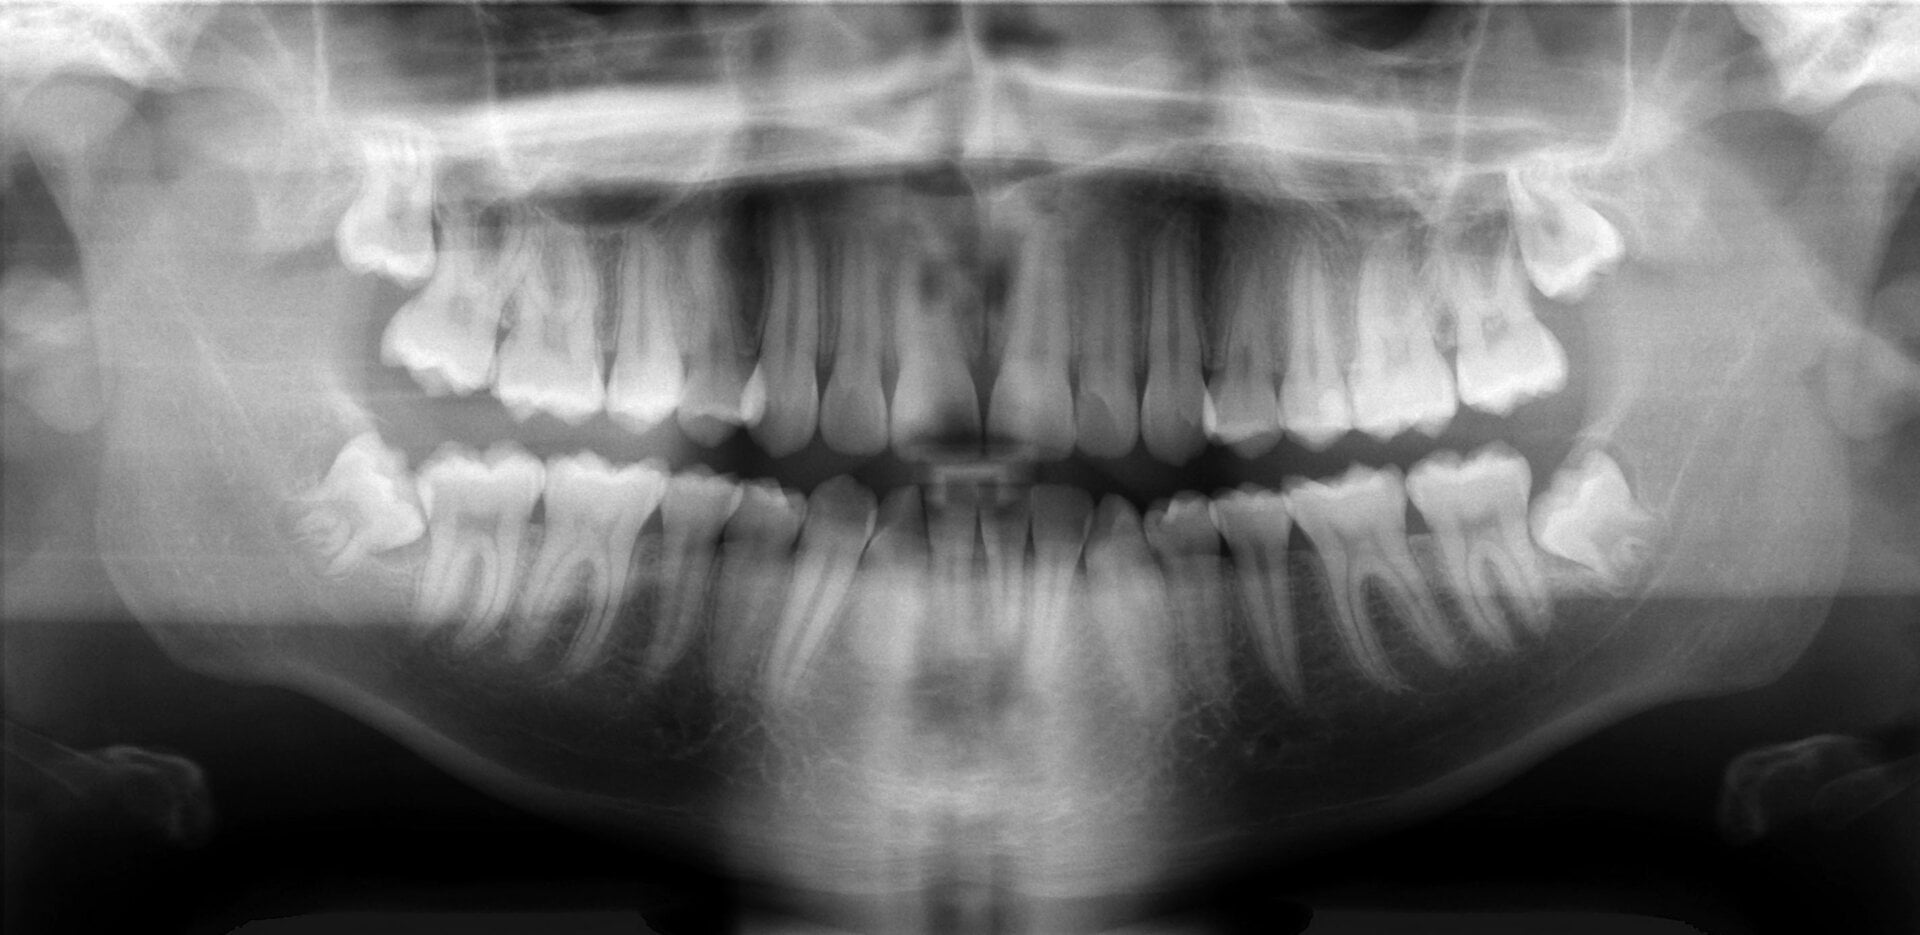

Descubren que un nuevo fármaco contra el Alzheimer es capaz de regenerar los dientes con caries

Quizá en el futuro cercano podamos visitar menos al dentista. Un equipo de médicos del Colegio Imperial de Londres ha descubierto un interesante efecto secundario en una droga contra el Alzheimer: hace que los dientes se regeneren.

Lo que han encontrado es que el tideglusib activa las células madre en la pulpa del diente (la parte blanda central) y las convierte en odontoblastos. Estas células son las encargadas de producir dentina, el material natural del que están rellenos los dientes.

Este proceso se suele dar de manera natural para reparar pequeñas grietas y desperfectos, pero no ocurre lo mismo con grandes zonas dañadas como las caries. El tideglusib no nos evitará completamente tener que ir al dentista. Las caries aún deben ser atendidas por un profesional. Lo que nos evitan es la segunda parte del tratamiento: el empaste o amalgama.

Puede parecer poco, pero sería una gran ventaja. El material con el que los dentistas nos rellenan el hueco de una caries no es tan resistente como el material natural del diente. Se agrieta, se deforma, y tarde o temprano hay que retocarlo o sustituirlo completamente.

La gran duda es si el fármaco será igual de efectivo en seres humanos. De momento, y como explican en el estudio publicado en la revista Scientific Reports, solo se ha probado en ratas. Cabe la posibilidad de que las caries humanas sean demasiado grandes para que el tideglusib logre rellenarlas. El siguiente paso es probar el fármaco en ensayos clínicos con pacientes humanos. Si funciona, podría ser el fin de los empastes tal y como los conocemos. [Scientific Reports vía The Guardian]